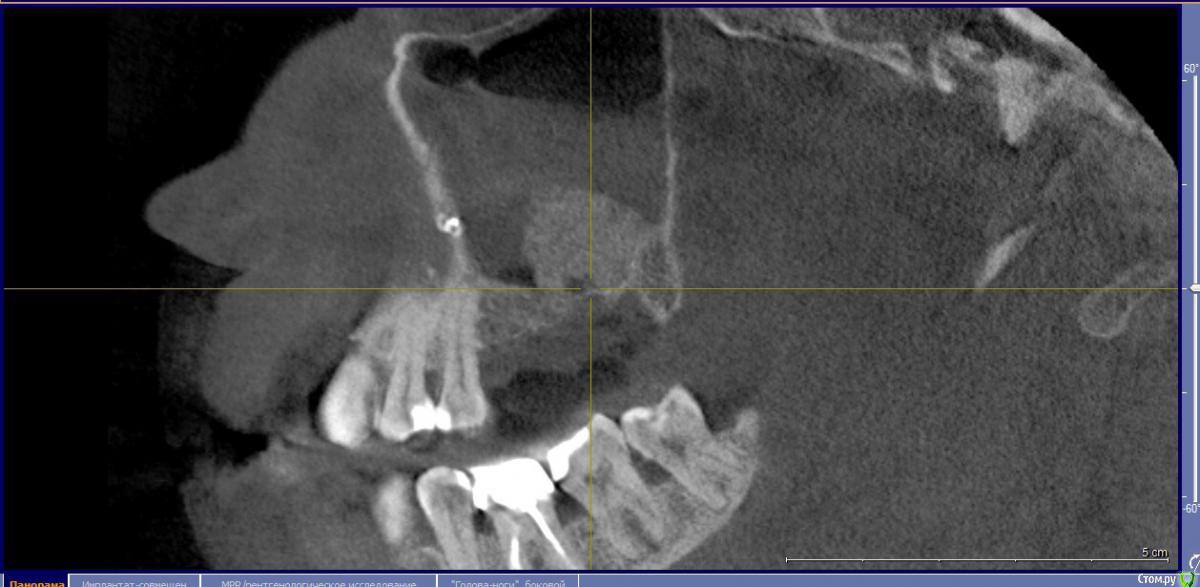

Кариес+ Опубликовано 27 августа, 2016 Поделиться Опубликовано 27 августа, 2016 Подготовили перед операцией кт , оказалось 15го года, не обратил внимание, пазуха была чиста . После операции сделал кт , а там пазуха полная и с синусом прокосячил . Что ожидать коллеги, как спасти ситуацию Ссылка на комментарий

Кариес+ Опубликовано 27 августа, 2016 Автор Поделиться Опубликовано 27 августа, 2016 Да это кортикалка , оттек может быть связак с моим вмешательством? Это может быть кровь или физ.раствор от пьезотома? Если предположить что я прорвал синус Ссылка на комментарий

Доктор Добрых Дел Опубликовано 27 августа, 2016 Поделиться Опубликовано 27 августа, 2016 Это не жидкость. Отек слизистой. Думаю материал в кость вряд ли превратится так как с костью практически не контактирует, так что лучше сразу убрать и переделать. Ссылка на комментарий

колесников Опубликовано 27 августа, 2016 Поделиться Опубликовано 27 августа, 2016 Дайте мне надежду в которую я буду верить))Ну отёк может и сойдёт,только синуслифтинг не удался. Отслоили недостаточно,весь графт на щёчной стенке остался. Ждать смысла нет. 4 Ссылка на комментарий